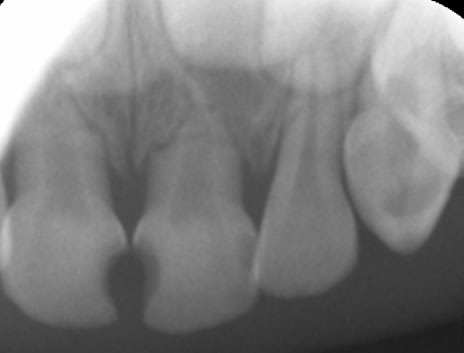

Radios de contrôle.

Pour 65, on voit sur la vue clinique une large canal palatin ovalaire. L'image radiographique correspond probablement à la fusée d'IRM dans l'entrée de ce canal. Je ne pense pas avoir perforé (j'espère !).